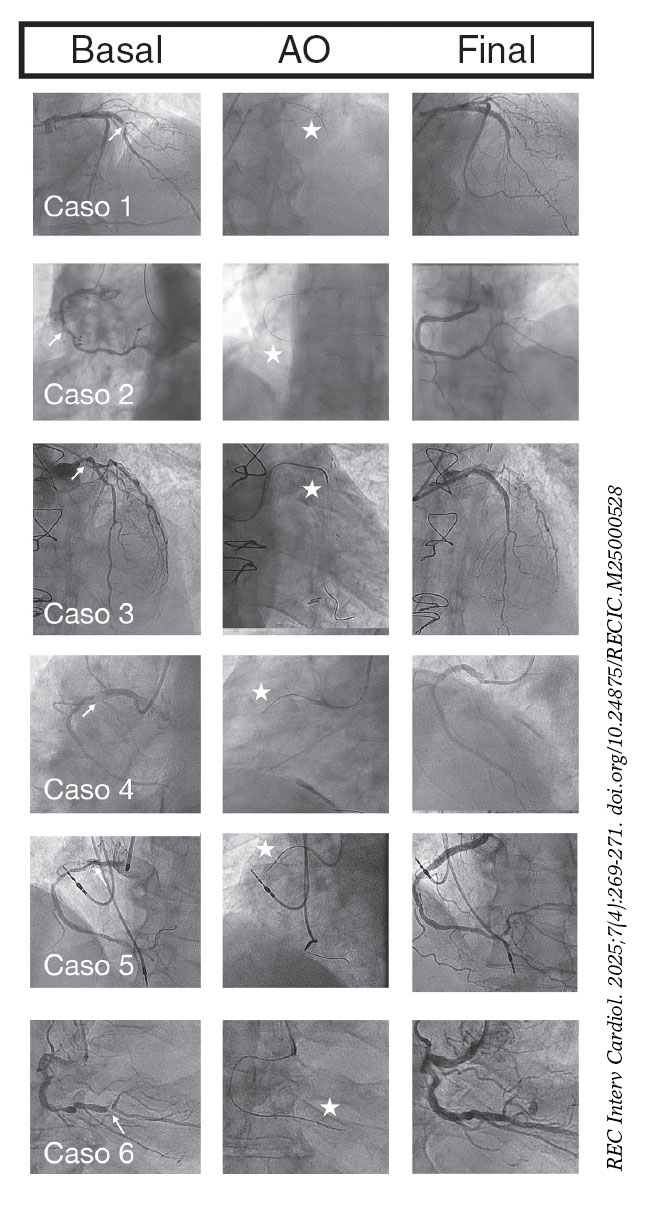

En todos nuestros casos tuvo éxito la AO, con cruce de la corona a través de la lesión que permitió posteriormente la angioplastia sin complicaciones mayores. En la figura 1 se ofrece un resumen con las imágenes angiográficas de cada caso.

Figura 1. Coronariografía basal, aterectomía orbitacional (AO) y coronariografía final. Las flechas señalan la lesión no cruzable, y las estrellas, la corona de la AO.